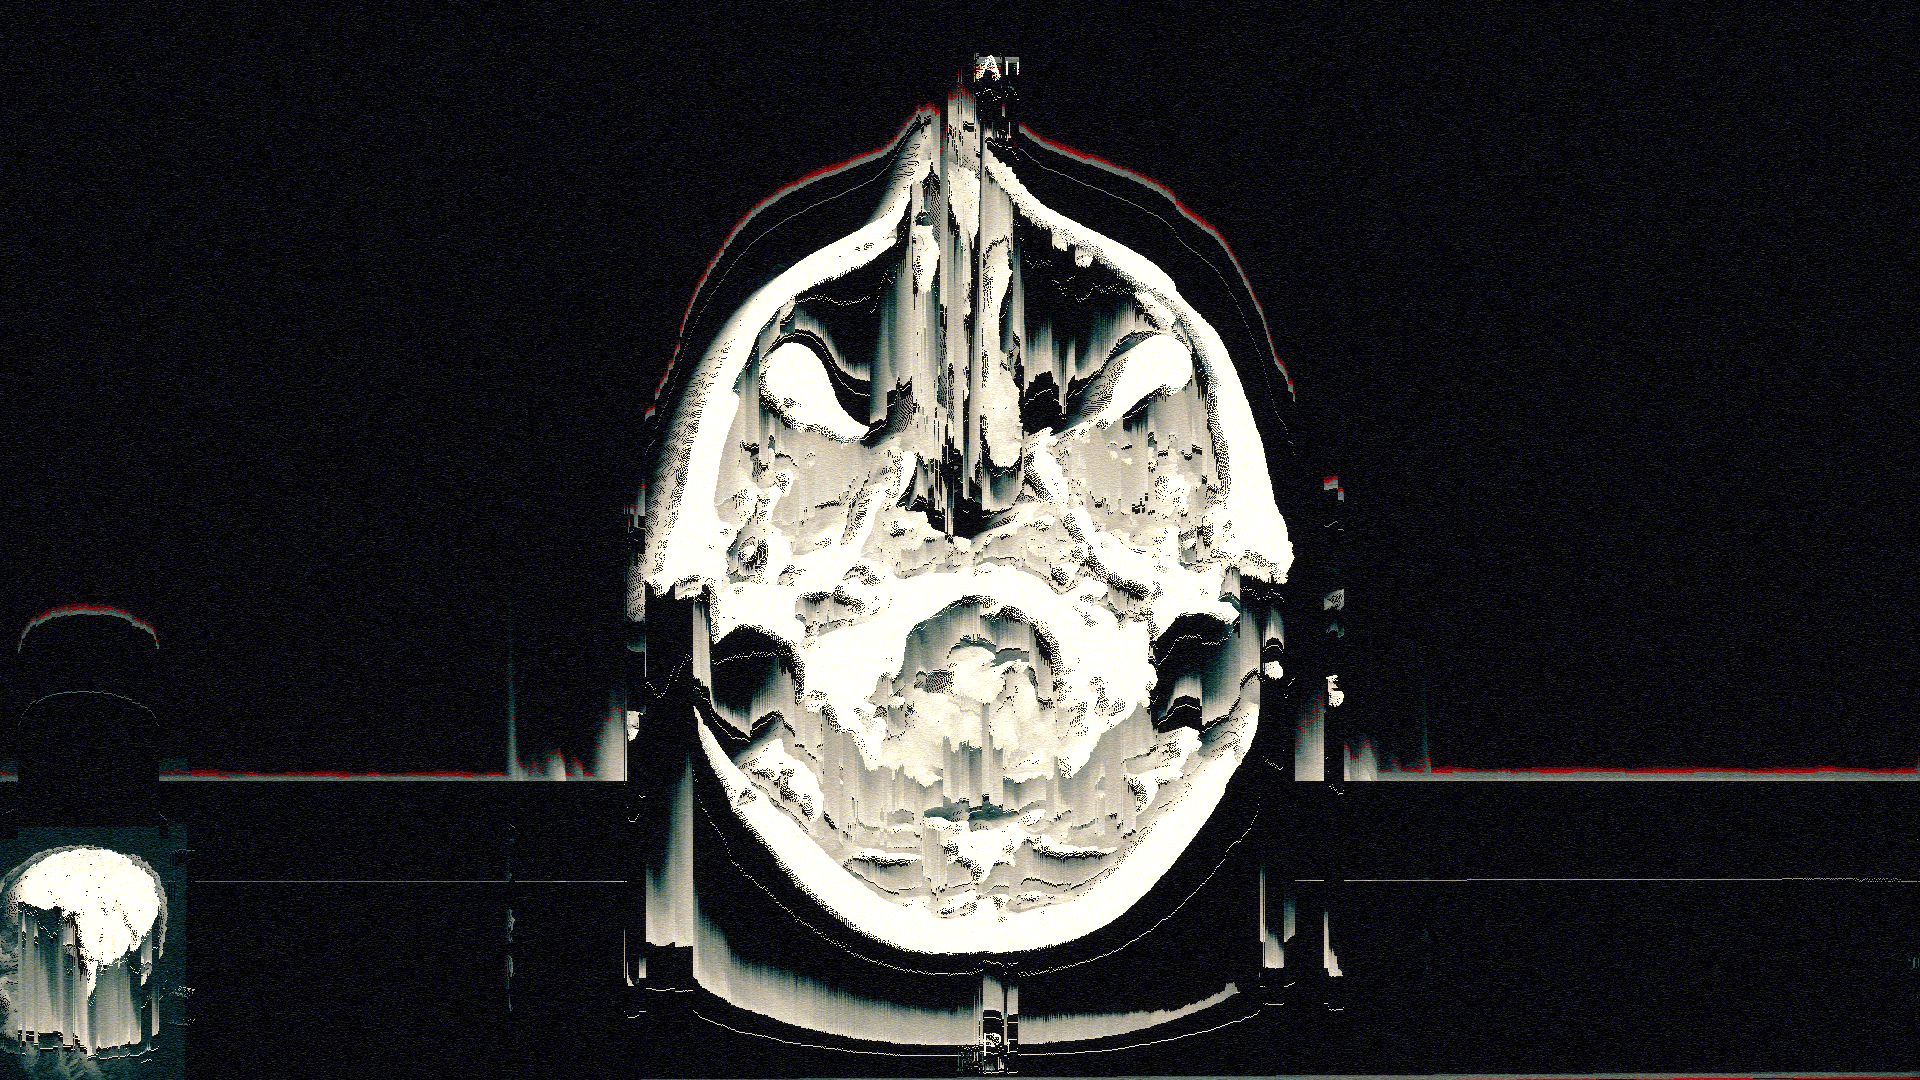

I recently developed style frames and animations for a television commercial. The main topic of the ad was to reflect Alzheimer's disease and what happened in the patient's brain.